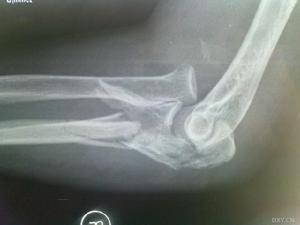

1.X線肘關節側位像 因無移位骨折在正位像上往往表現不出。

2.雙側X線攝片對比 肘關節化骨中心在融合前有可能與骨折混淆,可疑者應攝健側對比。

1.X線肘關節側位像因無移位骨折在正位像上往往表現不出。2.雙側X線攝片對比肘關節化骨中心在融合前有可能與骨折混淆,可疑者應攝健側對比。